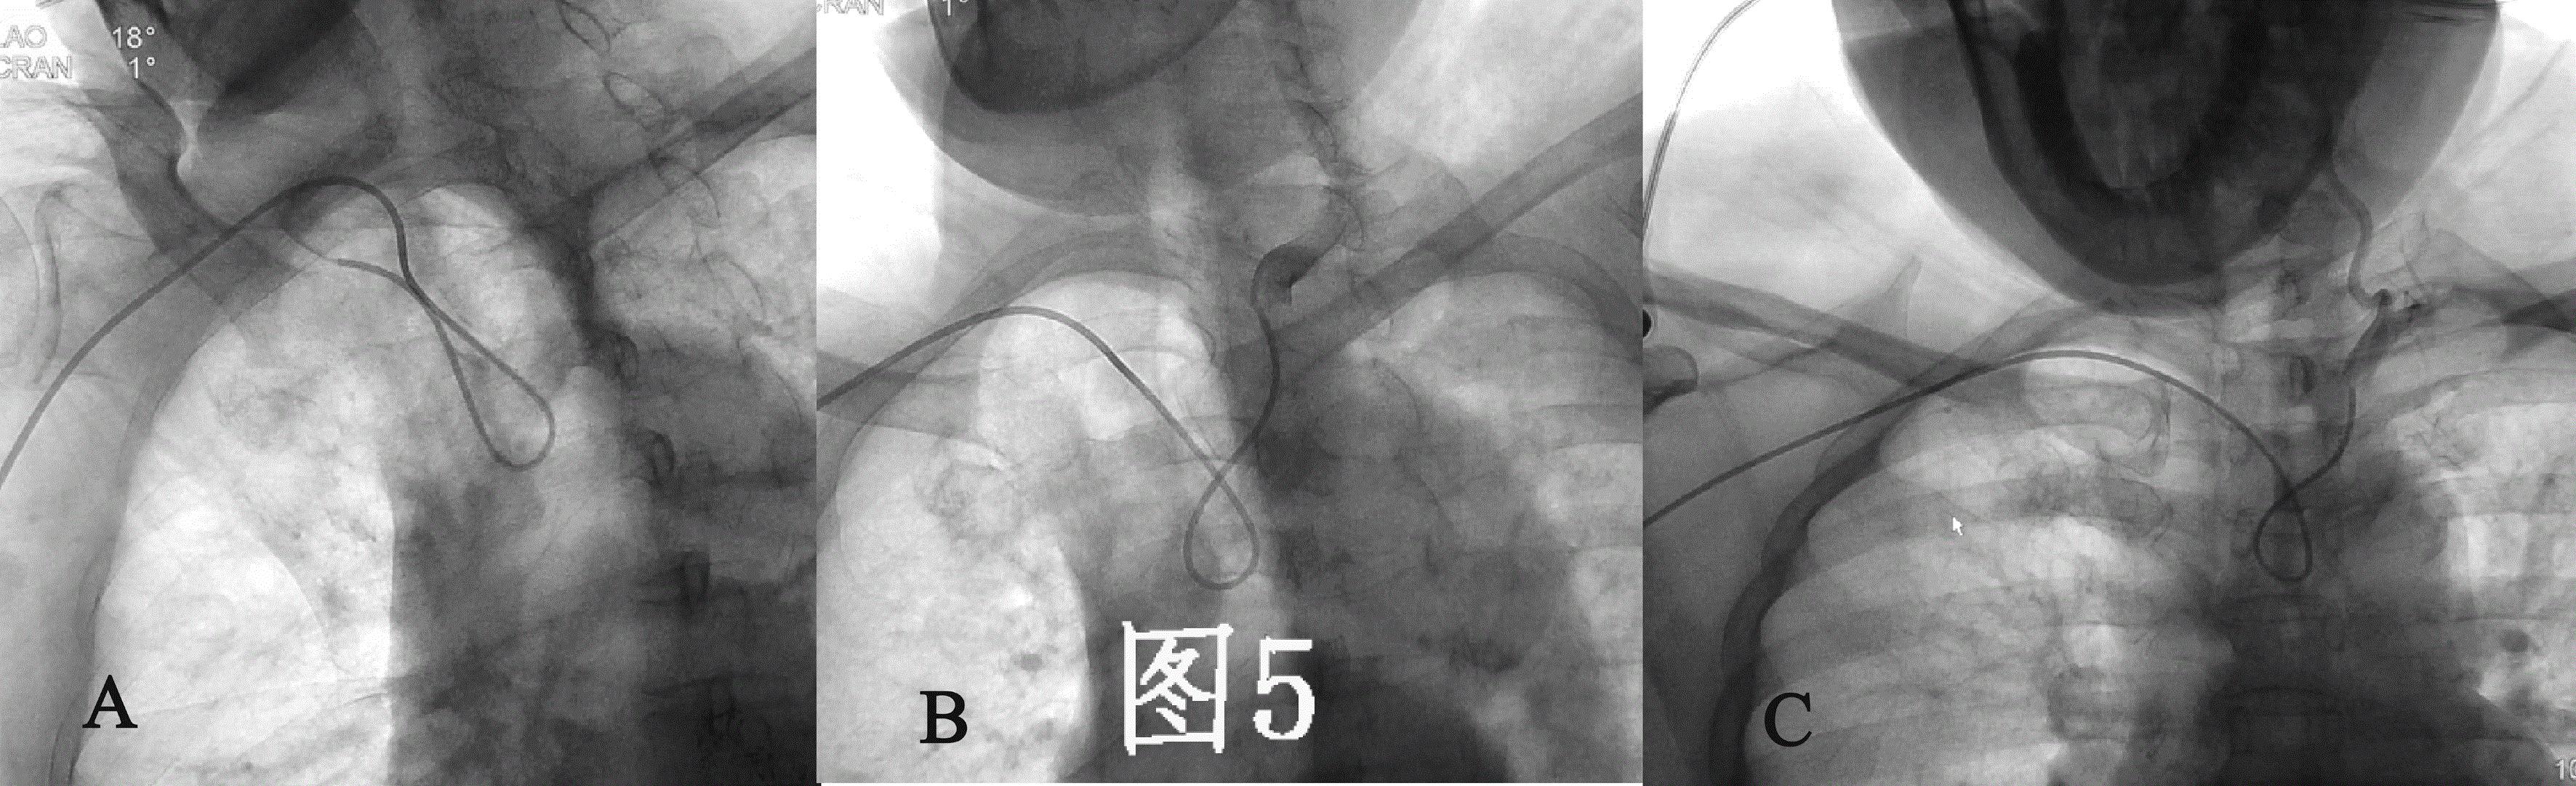

目前经桡动脉全脑血管造影通常选用的导管为西蒙造影导管,依据导管外形尺寸的大小分为三种型号,其中II-III型管均可被用于经桡动脉全脑血管造影(图4 A、B)。 西蒙造影导管的形状是按照经股动脉入路设计的,第一个弯在导管远端越过主动脉弓后可骑跨在主动脉弓上作为支点,而第二个弯曲则引导导管头端向上翘起,可选择性的进入无名动脉、左颈总动脉或左锁骨下动脉其中的任何一支血管(图3A)。 但是,在经桡动脉入路时,导管的第一弯曲无法骑跨在主动脉弓上,导管的第二弯曲引导的导管末端方向向下,这与脑主要血管的开口方向相反(图3B)。

因此, 需使用西蒙管的反勾技术(使导管扭曲呈“8”字形而不是导管原塑性的形状,使得导管末端的方向朝上)才能实现血管的超选(图5),这造成导管的操作困难